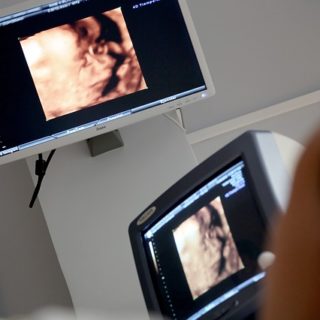

= Gefäßultraschall Die Dopplersonographie ist eine spezielle Form der Ultraschalluntersuchung mit der die Blutströmungsgeschwindigkeit der Gefäße des Kindes gemessen werden kann. So lässt sich...

Synonyme; „großes Screening“, Organultraschall, siehe auch Dopplersonographie Der Feinultraschall, der „große Ultraschall“ wird meist zwischen der 19. und 24. Woche durchgeführt! Er wird auch...

Messung der Nackentransparenz Die Nackenfaltenmessung bzw. eigentlich die Messung der Nackentransparenz erfolgt meist zwischen der 10. und 14. Schwangerschaftswoche (idealerweise in der 11.SSW) , da...